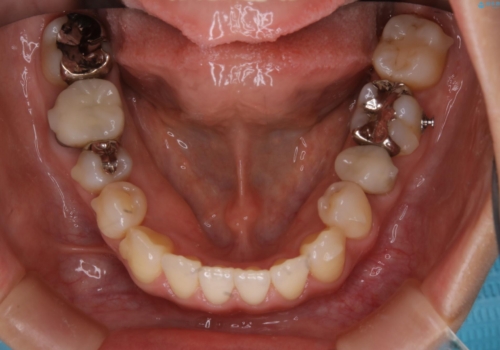

前歯が内側に入っている:インビザライン治療

- 上の前歯は内側に入っていることが気になりご相談にいらした方です。インビザラインにて治療を行いました。

1週間でのマウスピース交換を指示していましたが、20時間以上使えない時があると不安との事で、2週間ごとの交換にしていました(実際はほとんど20時間以上使用できていたようです)。治療終了まで時間はかかりましたが、最終的に綺麗に並べることができ、大変喜んでいただけました。